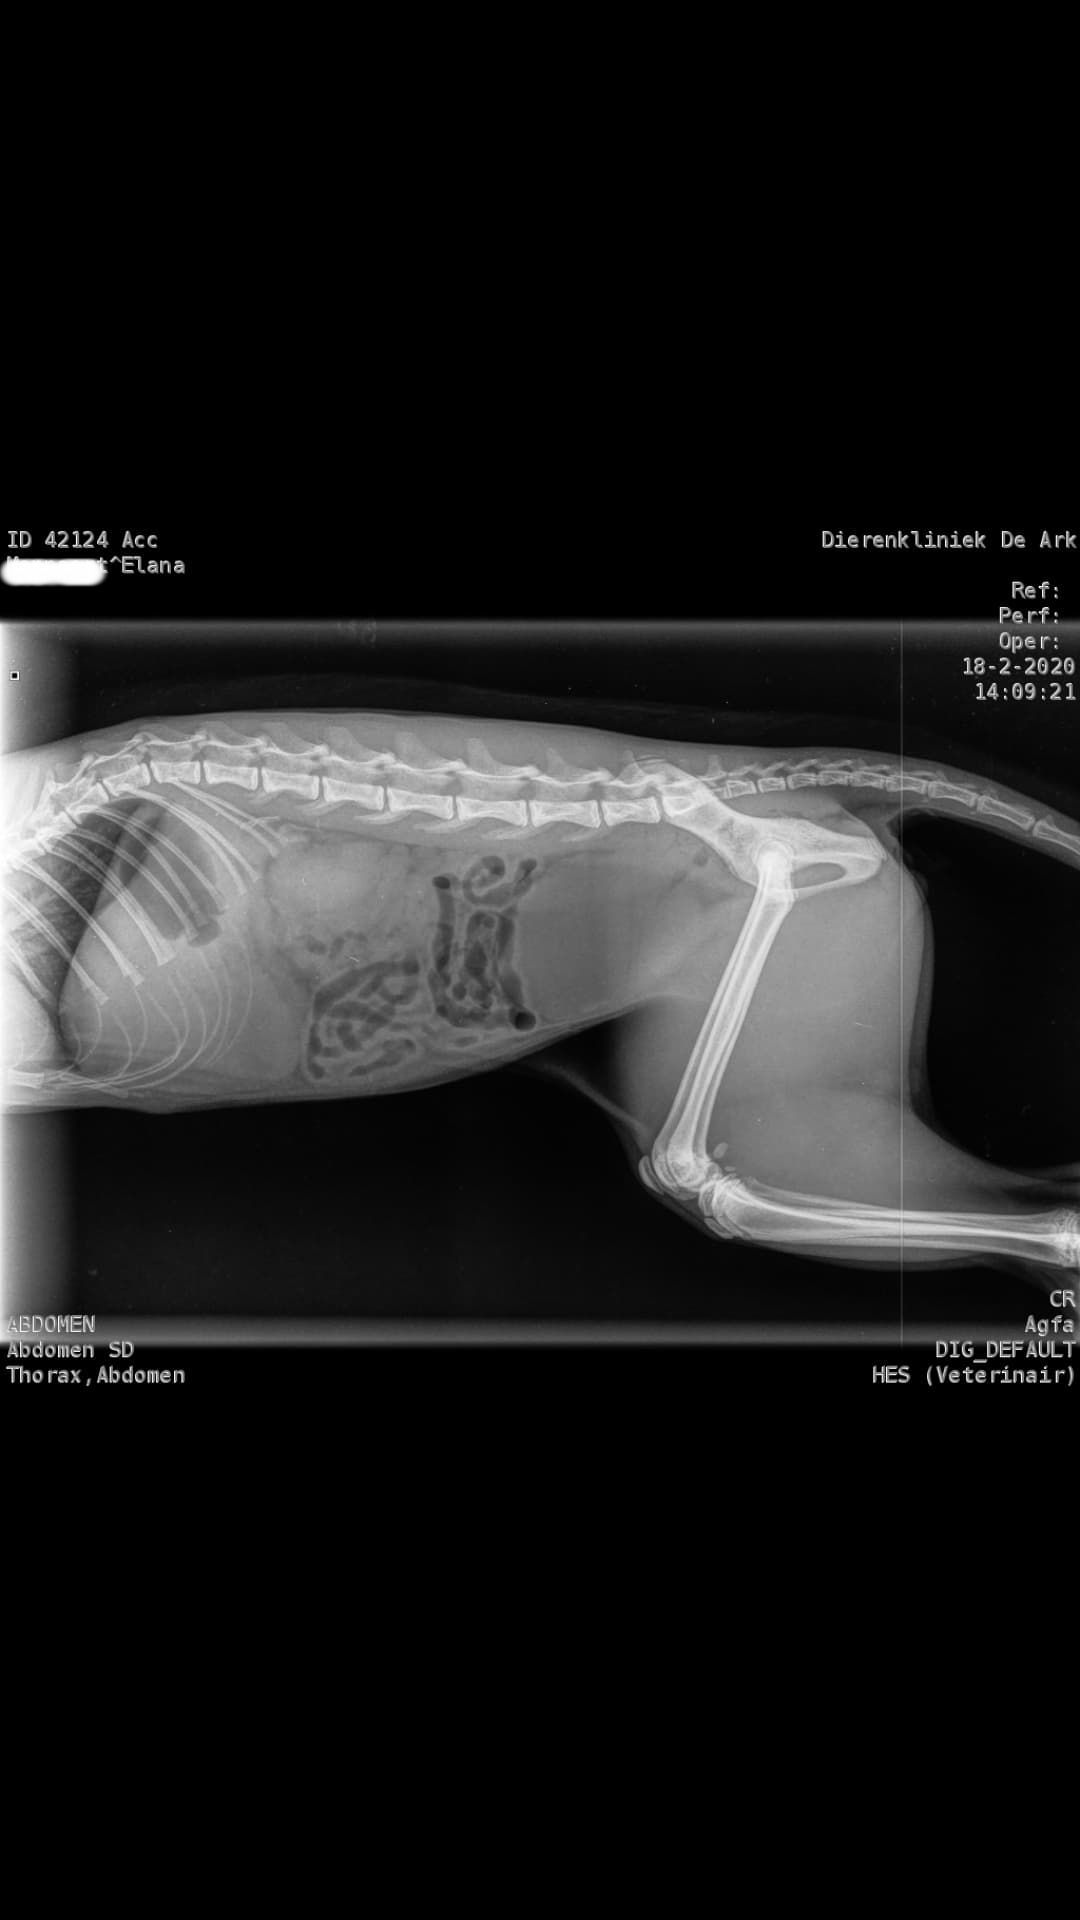

Dinsdag 18 februari 2020 - 84 + 25

39 graden gemeten bij de dierenarts. De bloedonderzoeken laten al zien dat de waardes enorm veranderd zijn en reden zijn tot het hebben van grote zorgen. Elana is verder volledig nagekeken. Een eventueel ongeluk is uitgesloten d.m.v. rontgenfoto's.  Haar A/G waardes zijn nu gezakt naar 0,57 dit was op dag 82 van de behandeling maar liefst 1,13

Ter vergelijking de 2 laatste laboresultaten naast elkaar.

Dag 82 van de 1e behandelronde en nu na 25 dagen stoppen en ze een terugval heeft.